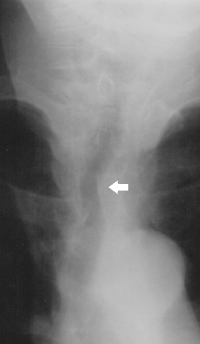

Hipertireoz (Tireotoksikoz) – qalxanabənzər vəzinin xəstəliyi olub qanda tireoid hormonlarının miqdarının artması ilə xarakterizə olunur. Bir çox hallarda buna səbəb diffuz toksiki zob (Bazedov-Qreyvs xəstəliyi) və qalxanabənzər vəzinin funksional avtonomiya xəstəliyidir (toksiki adenoma, çoxlu düyünlü toksiki zob). Bu xəstəliklər zamanı qalxanabənzər vəzidə çoxlu miqdarda tiroksin (T4) və triyodtironin (T3) hormonları əmələ gəlir ki, bu da zülal və lipid mübadiləsinin, ürək-damar və sinir sisteminin funksiyalarının pozulmasına gətirib çıxarır.

![]() Triyodtironin tiroksinlə birlikdə qalxanabənzər vəzinin əsas hormonlarından biridir. | |